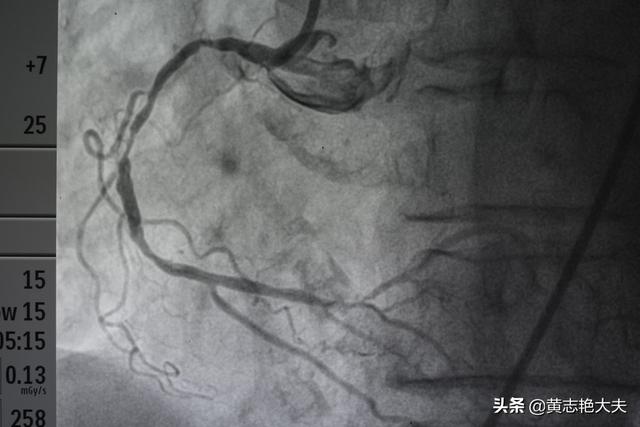

- Les produits de contraste "éclairent" les artères coronaires :Les artères coronaires du corps humain sont relativement petites : le tronc principal des artères coronaires ne mesure que cinq ou six millimètres, certaines des branches les plus importantes mesurent environ deux ou trois millimètres, et les autres sont des branches encore plus petites ; ces vaisseaux sanguins sont reliés aux tissus environnants et sont recouverts par les os, les muscles, etc. devant eux. Lors de la coronarographie, un agent de contraste est injecté à l'intérieur du cathéter mentionné plus haut afin de remplir les artères coronaires d'agent de contraste.L'agent de contraste est un médicament imperméable aux rayons X qui "illumine" les artères coronaires pendant la coronarographie afin que nous puissions voir clairement la distribution, la taille et la présence de sténoses et d'obstructions dans les artères coronaires.

- La DSA (Digital Subtraction Angiography) est une caméra pour les vaisseaux sanguins :L'équipement utilisé pour prendre des photos des artères coronaires mentionné plus haut est le DSA, qui est en fait également une forme d'examen aux rayons X, capable de prendre des photos et d'enregistrer des vidéos des différentes artères coronaires sous de multiples angles tout en injectant le produit de contraste, ce qui peut être considéré comme un angle de 360 degrés sans issue, et ces photos et vidéos peuvent être déposées sur un CD-ROM pour être facilement conservées et analysées.C'est parce que la coronarographie permet d'obtenir des photographies et des vidéos d'une telle clarté que la coronarographie est l'étalon-or du diagnostic de la maladie coronarienne.

La coronarographie consiste à enfiler une aiguille dans l'artère fémorale, à envoyer un tube jusqu'à l'emplacement de l'artère coronaire, à appliquer un produit de contraste iodé et à montrer l'artère coronaire, ce qui permet de diagnostiquer les maladies congénitales de l'artère coronaire, l'athérosclérose, les anévrismes, les malformations artérielles et d'autres maladies, dont la plupart sont des athéroscléroses qui entraînent un rétrécissement de la lumière. Le degré de sténose peut être évalué et, dans le cas d'une sténose grave, avec infarctus du myocarde, un stent peut être directement mis en place pour ouvrir la lumière rétrécie et rétablir le flux sanguin à des fins thérapeutiques.